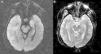

Presentamos el caso clínico de una mujer de 71 años con dislipemia, hipotiroidismo y carcinoma ductal de mama con exéresis radical, y actualmente en tratamiento con quimioterapia. Ingresó en el hospital por sepsis por Staphylococcus aureus meticilin-sensible (por infección del reservorio). Sufre de forma progresiva desorientación, habla repetitiva y somnolencia con evolución a status epilepticus, por lo que ingresó en el servicio de medicina intensiva (SMI). Se realizó tomografía computarizada (TC) craneal urgente, sin hallazgos significativos. A su ingreso presenta estado post-crítico, tras administración de benzodiacepinas intravenosas (IV), y temperatura de 38°C; el resto de la exploración por aparatos resultó normal. En la analítica reseñar plaquetas 22×109/l, creatinina 3,5mg/dl, urea 95mg/dl, proteína C reactiva 15,6mg/dl, resto normal. Se procedió a intubación orotraqueal y realización de punción lumbar (PL) con salida de líquido cefalorraquídeo (LCR) transparente a normopresión sin células, glucosa 68mg/gl y proteínas 64mg/dl (proteínas plasma 5,2g/dl). Se iniciaron sedo-analgesia, fluidoterapia, levetiracetam, tratamiento antimicrobiano IV de amplio espectro, que incluyó aciclovir. Se aislaron en broncoaspirado y un hemocultivo Klebsiella pneumoniae productora de betalactamasas de espectro extendido, sin condensación en la radiografía de tórax; urocultivo y cultivo de LCR negativos. LCR con reacción en cadena de la polimerasa (PCR) para virus de herpes simple (VHS), citomegalovirus (CMV), virus varicela-zóster (VVZ) y virus Epstein-Barr (VEB) negativos, con citología negativa para células malignas. Serologías para virus de la inmunodeficiencia humana, hepatitis, VHS, CMV y VVZ negativas para infección activa. CA 125 elevado (180,3U/ml); resto de marcadores tumorales normales. Anticuerpos (Ac) anti-DNA, antinucleares, c-ANCA y p-ANCA negativos. Hormonas tiroideas en rango dentro de la normalidad con tratamiento sustitutivo y Ac antiperoxidasa y antitiroglobulina negativos. Se realiza nueva TC con contraste que descartó enfermedad estructural, y PL de control con salida de líquido transparente a normopresión con perfil bioquímico normal sin células, y negativo para malignidad. Dado el bajo nivel de conciencia se realiza electroencefalograma (EEG) que es compatible con efecto de la sedación y resonancia magnética nuclear (RMN) cerebral con el siguiente resultado: en la secuencia potenciada en T2 hiperintensidad de la región hipocámpica de predominio izquierdo, en la secuencia en difusión se observa hiperintensidad con discreto descenso del coeficiente de difusión aparente (ADC) en la región hipocámpica del lóbulo temporal izquierdo. Tras la introducción de contraste paramagnético no se observan captaciones (figs. 1 y 2A y B).

Ante los datos clínicos y la neuroimagen característica se planteó el diagnóstico de EL; se solicitaron Ac onco-neuronales en sangre y LCR (frente NMDA, IA-2, GAD, Hu, Yo, Ri, PNMA2, CV2, antifisina, titina, recoverina y SOX1) que fueron negativos. Se inició tratamiento con metilprednisolona IV 1mg/kg/d con recuperación neurológica lentamente favorable. Alta del SMI a los 35 días y del hospital a los 20 días, después tratamiento con prednisona vía oral 1mg/kg/d durante 3 meses, tras los cuales presentó recuperación neurológica «ad integrum».

El cuadro clínico de la EL se caracteriza por la aparición subaguda2 de alteraciones neuropsiquiátricas diversas que incluyen, entre otras, deterioro cognitivo, convulsiones, depresión, irritabilidad, alucinaciones y pérdida de memoria reciente3,4. En la mayoría de los casos el LCR5 muestra cambios inflamatorios con proteinorraquia y/o pleocitosis discretas, sin hallazgos patognomónicos. La TC5 habitualmente es normal, sin captación de contraste y la RMN cerebral5 en el 70% de los casos muestra hiperintensidad de ambos lóbulos temporales en forma asimétrica, especialmente en las secuencias T2 y FLAIR, que no realza con contraste. El EEG puede mostrar lentitud temporal o difusa, espigas temporales, actividad convulsiva focal temporal o generalizada.